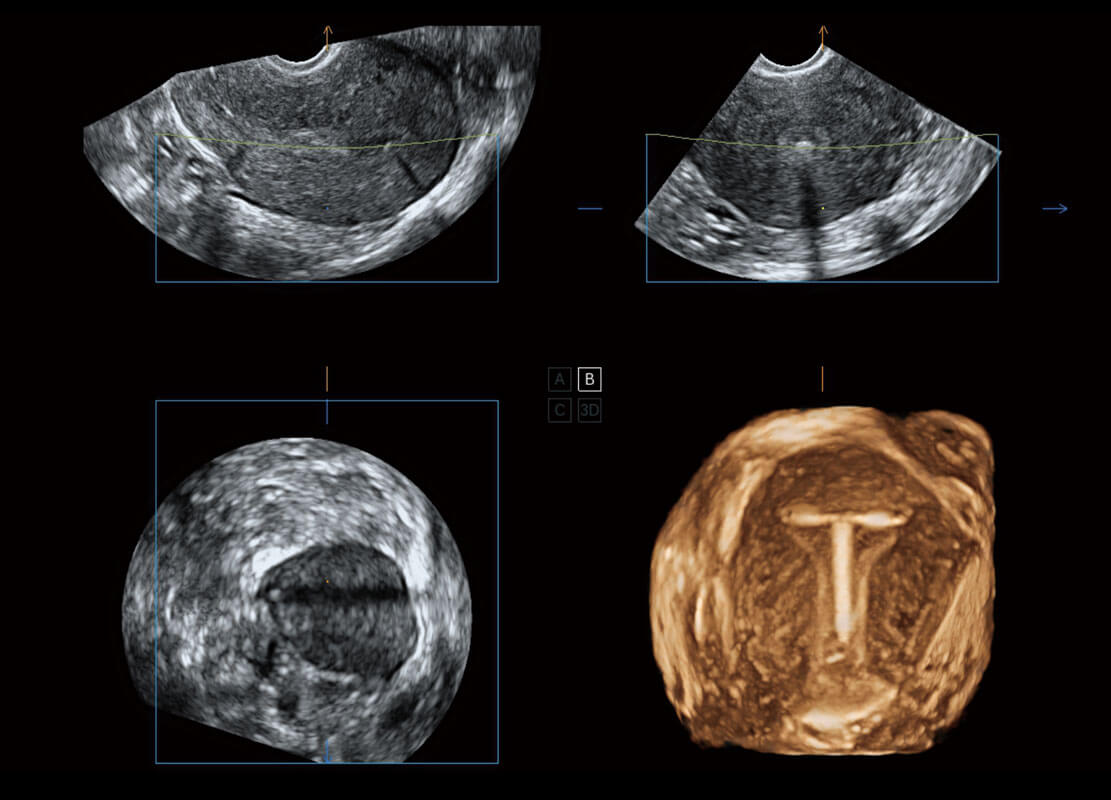

P60搭载一系列胎儿心脏成像技术,实现精细的胎儿心脏评估。

四腔切面

四腔心血流

右室双出口

胎心容积成像